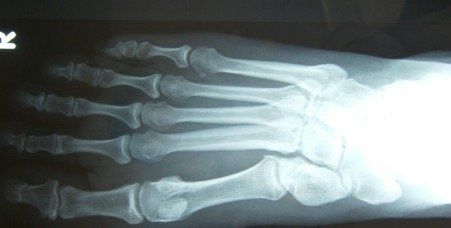

Midfoot arthritis refers to arthritis in the middle part of the foot. There are a number of joints that make up this part of the foot and arthritis in this area presents with degenerative changes. Degenerative changes are depicted by pain in the area, instability of the joint, narrowing of the joint space, osteophytes or bone spurs, cystic areas within the bone, damage to the joint cartilage, and laying down of extra bone.

Surgery for midfoot arthritis ranges from simple to more complex procedures. Surgery may involve a “clean-up” of the joint by removing damaged cartilage and bone spurs, resection of a part of the joint, fusion (stiffening) of one or more joints. Medical imaging, such as x-rays and MRIs are usually obtained prior to surgery to determine the extent of the injury and to plan for the proposed surgery.